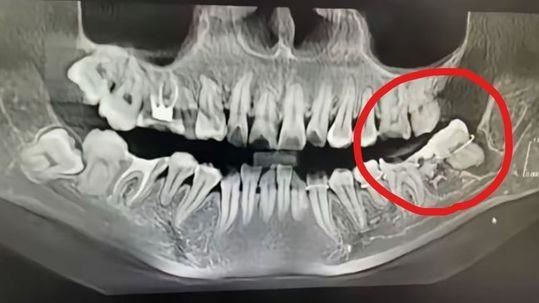

▲醫生拔錯牙,用鐵絲綑綁牙齒(紅圈處)硬塞回牙槽。(圖/翻攝自抖音)

綜合陸媒報導,一名34歲的吳姓女子12日前往安慶市立醫院口腔科接受智齒拔除手術。根據吳芳芳生前在社交網站的描述,醫師在施打麻藥後錯將一顆健康的門牙拔除,應拔除的智齒則仍留在口中。更糟糕的是,醫師未妥善補救,而是用鐵絲將拔錯的牙齒綑綁並強行塞回牙槽,過程中未重新施打麻藥,造成吳女極大痛苦。